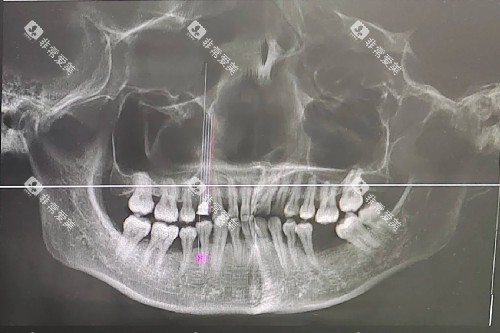

科室拥有口腔全景机、口腔 CT、智能化牙片机等可靠的影像设备,能够为医生提供更准的诊断依据。

这些设备可以清晰地显示牙齿和颌骨的结构,帮助医生更更准地制定治疗方案。